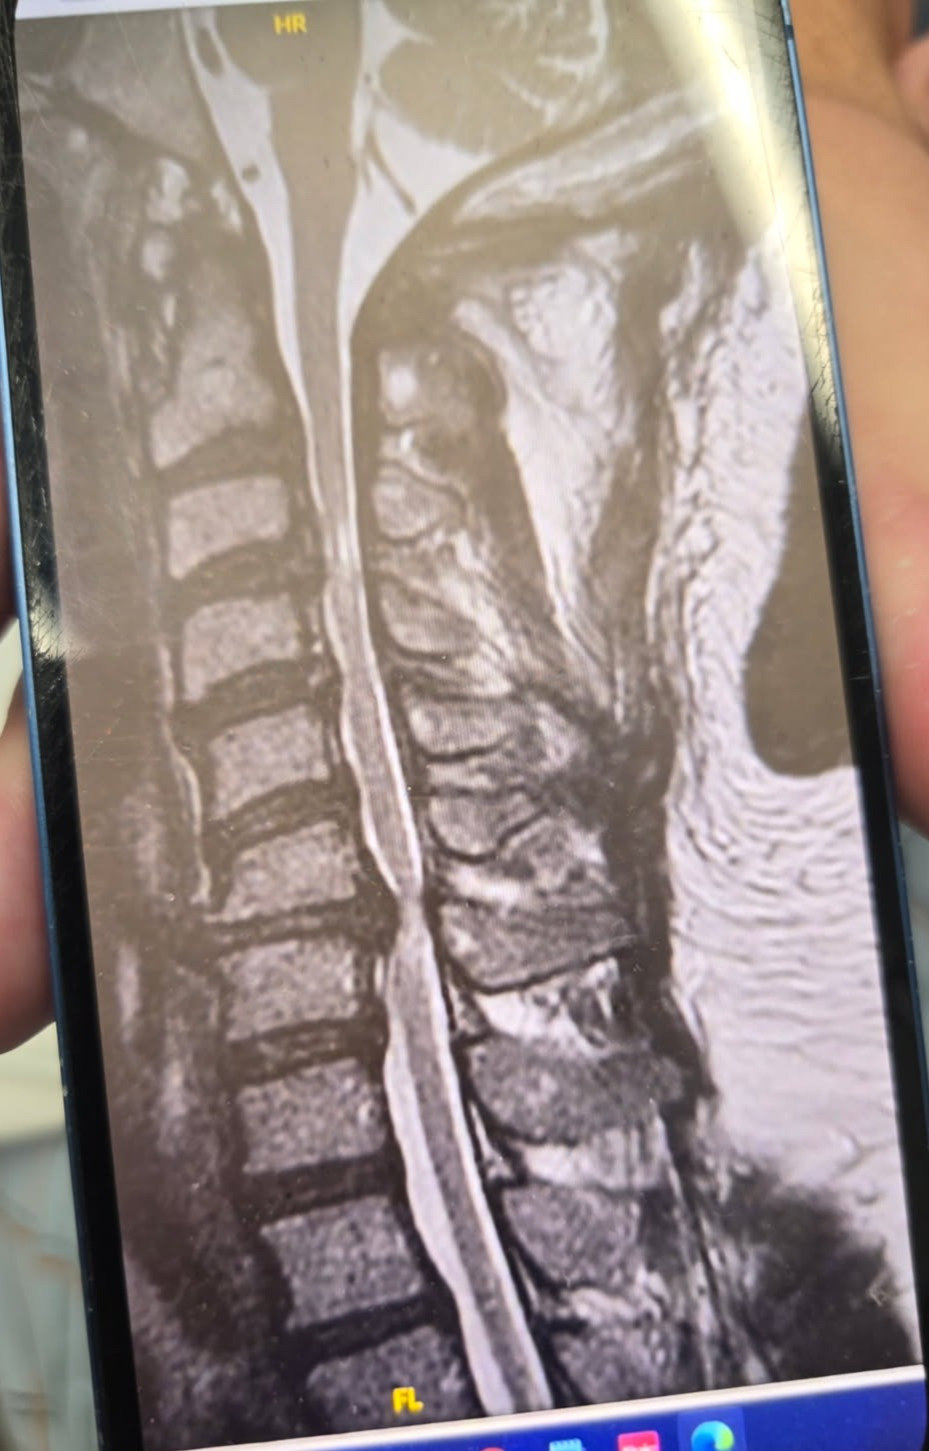

Main fundraiser photo

Our friend and business colleague traveled from Texas to the New Jersey/New York City area at the end of July, eager to share his expertise at a major conference. Instead of podium lights and applause, he was met with sudden, severe pain—later diagnosed as spinal stenosis. Facing an urgent situation, he underwent emergency surgery in New Jersey because traveling home would have been too dangerous.